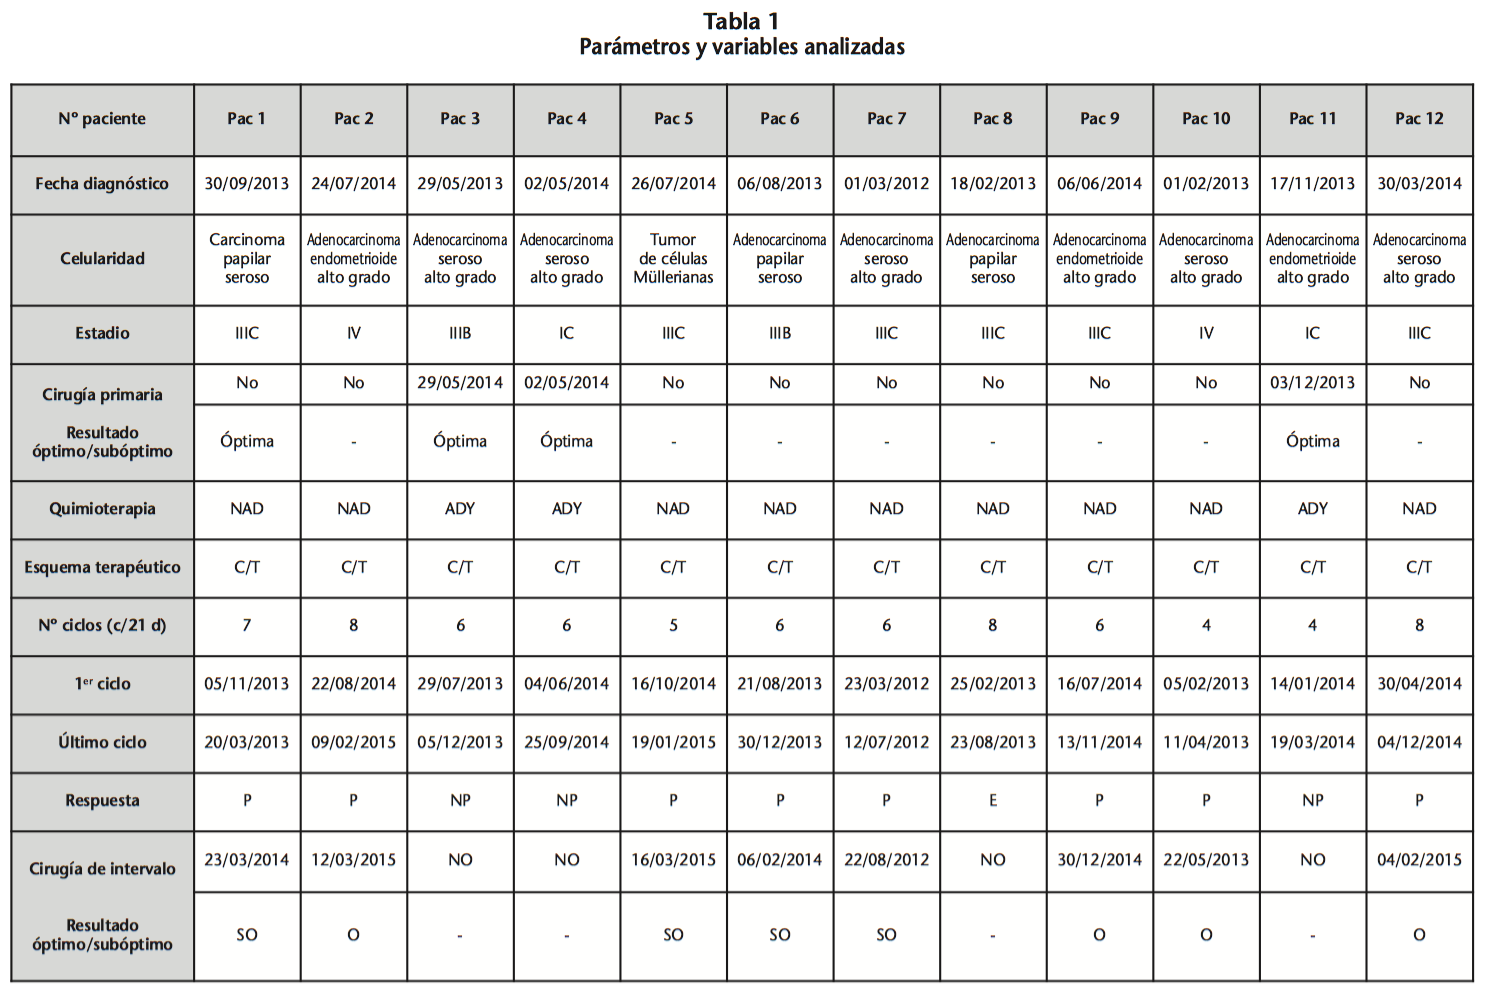

Pase para saber Psicológico pueblo Marcadores tumorales en el diagnóstico de cáncer epitelial de ovario: caso de estudio Tumor markers in the diagnosis of epit